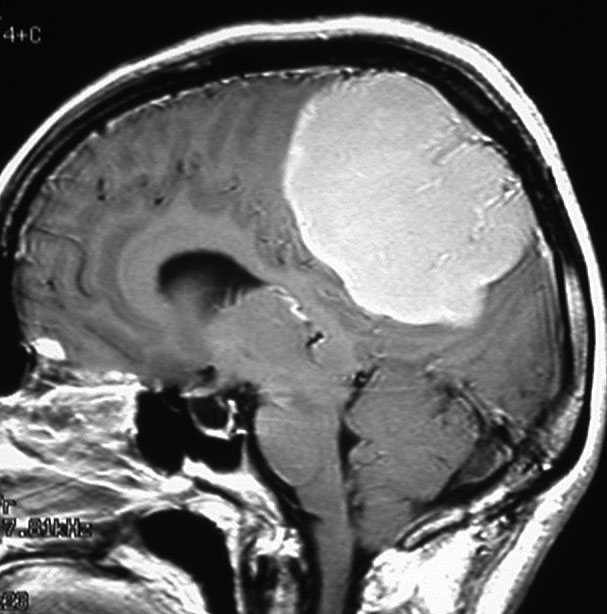

左は,造影剤を使ったガドリニウム増強MRIです。腫瘍が白く丸く見えます。右はフレア画像で,腫瘍の周囲の脳浮腫(脳のはれ)です。左前頭葉が,かなり強くはれています。この腫瘍は小さいのですが,脳のはれが強すぎるので手術摘出したほうがいいです。浮腫が悪化すると,てんかん発作や認知機能低下がでる可能性があります。

MRIでの髄膜腫の見え方は撮影の仕方によっていろいろです。左からT1強調画像,T2強調画像,フレア画像といいます。腫瘍の横に小さく白い領域がありますが,これは脳の腫れた部分で脳浮腫といいます。髄膜腫があると周囲に脳浮腫が生じることがあります。

最も見やすいのが,ガドリニウム造影剤を注射して撮影するものです。一般的に髄膜腫は造影剤で白く映し出されます。この腫瘍は左脳側にあります。MRIの軸面という輪切りの写真では左右が逆になりますから注意してください。脳を下から見た図になっています。MRIはいろいろな方向から腫瘍を見ることができますが,右は冠状断という正面から見た図です。よく見ると腫瘍の上と下のはじっこに線状に糸を引いたように造影される部分があります。これをテールサイン(しっぽのサイン)といいます。腫瘍が硬膜に沿って延びている可能性があることを示しています。

手術後のMRIです。腫瘍は全部取れていて後遺症もありません。圧迫されて変形していた脳はきれいに元に戻っていますし脳浮腫も消えました。一般的に若い人の脳ほどきれいに元に戻ります。注意しなければならないのは,少しでも取り残した場合には,何年か後に10%-20%くらいで再発があることです。もちろん完全に取れた時の再発はほとんどありません。